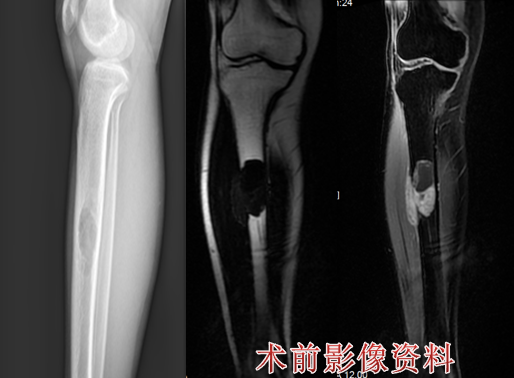

病例一

患者为一名14岁女孩,经检查,发现左股骨下段有肿物,时间长达6个多月,被诊断为普通型骨肉瘤。

2.png

在医院骨科骨肉瘤组长王新家主任医师的带领下,王伟东副主任医师及MDT团队成员充分讨论,通过制定详细的诊疗方案、对患者进行术前新辅助化疗、定制个性化假体置换、实现保留胫骨侧骨骺的保肢治疗术,术后患者恢复良好。